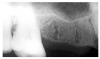

Dentin caries extends into the tooth dentin and can be recognized by noting the focal loss of dentinal radiopacity. Most commonly, this darkened dentin is located beneath carious enamel and, typically, the lateral dimension of the dentinal involvement exceeds that of the associated enamel caries (Figure 3). Dentin caries may be discerned interproximally, on the occlusal surface, buccally/lingually, or on root surfaces.

Figure 3 - Dentin Caries

Figure 3